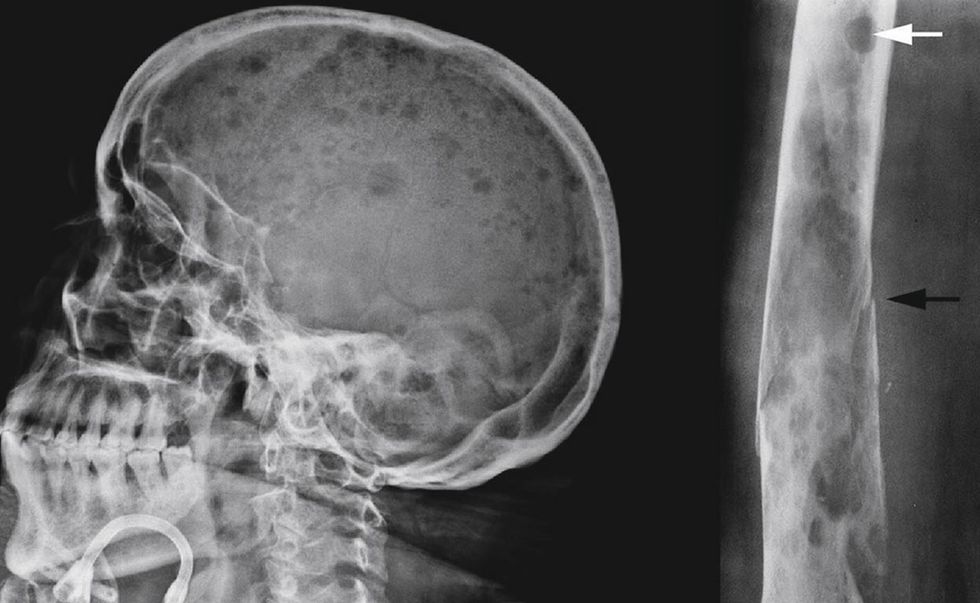

Tomografia e kompjuterizuar (CT): Ky test përdor një seri rrezesh X dhe një kompjuter për të krijuar imazhe tredimensionale të indeve dhe kockave tuaja. Nëse mjeku juaj dyshon se keni mieloma, ai mund të urdhërojë një skanim CT për të kërkuar dëmtim të kockave, ose nëse dyshon për limfoma, bëhet CT për të kërkuar për gjëndra, apo shpretkë te rritur.

Rezonanca magnetike (MRI): Mjeku mund të urdhërojë një MRI për të kërkuar shenja të leucemisë ose komplikimeve të limfomës që prekin shtyllën kurrizore.

Skanimi i tomografisë me emetim pozitron (PET): Mjeku juaj mund të urdhërojë një skanim PET për të kërkuar shenja të mielomës, leukemisë dhe limfomës.

• Mieloma multiple apo e shumëfishtë është një kancer që zhvillohet në palcën e eshtrave dhe prek qelizat plazmatike. Qelizat plazmatike janë qeliza të bardha të gjakut dhe pjesë e sistemit imunitar. Qelizat plazmatike (nganjëherë të quajtura qeliza B) prodhojnë antitrupa. Këto antitrupa, të quajtura imunoglobulina, ndihmojnë në luftimin e infeksionit. Mieloma e shumëfishtë ndodh kur qelizat e shëndetshme kthehen në qeliza jonormale që shumohen dhe prodhojnë antitrupa anormalë të quajtur proteina M. Ky ndryshim fillon një kaskadë çrregullimesh që mund të dëmtojnë kockat deri në thyerjen e tyre, të ndikojnë në veshkat tuaja duke dhënë dëmtim të tyre si dhe ndikojnë në aftësinë e trupit tuaj për të krijuar qeliza të shëndetshme të kuqe, të bardha të gjakut dhe trombociteve, që paraqiten me infeksione, pagjakësi dhe gjakderdhje.